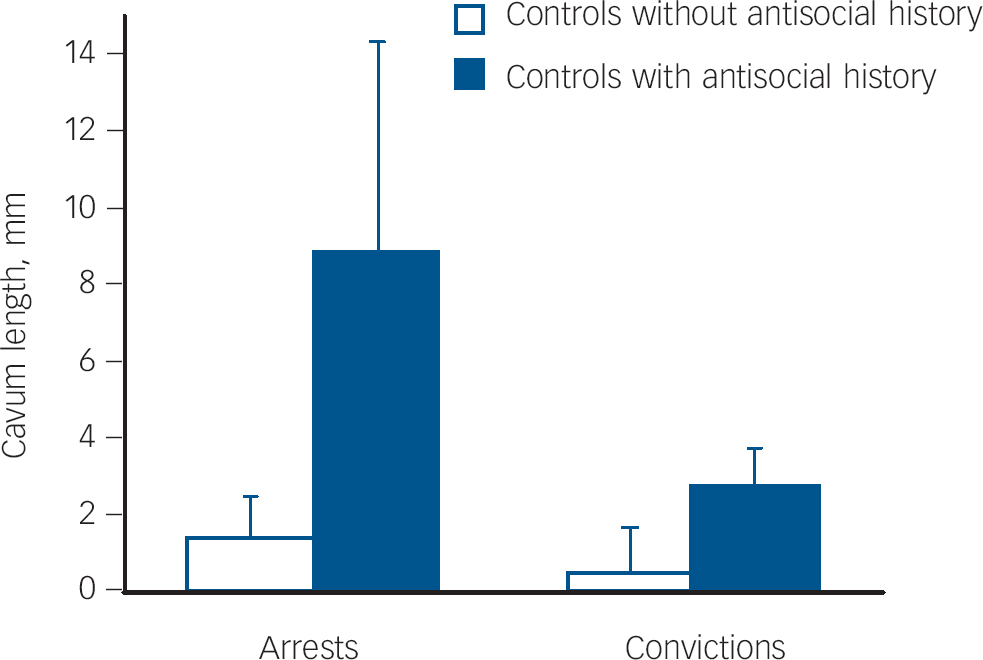

CSP in those lacking antisocial personality disorder but with some criminal offending

Individuals who did not have a diagnosis of antisocial personality disorder, but who nevertheless had been either arrested or convicted for a crime showed more evidence of CSP. Individuals in the control group were divided into those with a criminal history of arrests/convictions, and those without such a criminal history. Participants without an antisocial personality disorder but with a history of arrests had a longer CSP than those participants without an antisocial personality disorder but without arrests, F(1,61) = 5.57, P = 0.021, η = 0.084, with no main effect for gender (P = 0.94) or arrest×gender interaction (P = 0.60, Fig. 4). Participants without an antisocial personality disorder but with a history of convictions showed a trend for a longer CSP than those participants without an antisocial personality disorder but without convictions, F(1,61) = 3.34, P = 0.073, η = 0.052, with no main effect for gender (P = 0.61) or arrest×gender interaction (P = 0.94, Fig. 4).

Fig. 4 Mean length (mm) of cavum septum pellucidum with standard error bars in controls lacking a diagnosis of antisocial personality disorder but who nevertheless have either been charged (a) or convicted (b) for criminal offences compared with controls lacking both antisocial personality disorder and charges/convictions.